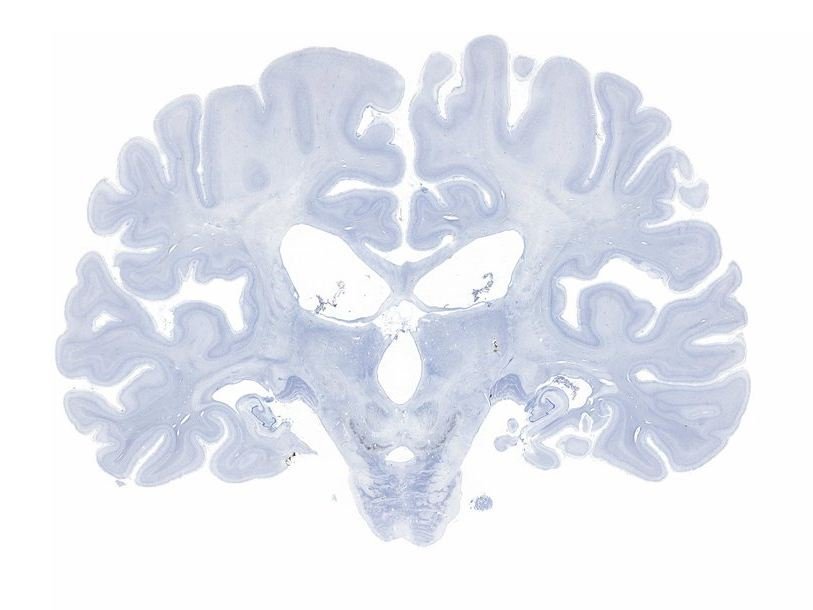

Исследователи под руководством Сьюзен Коркин на основе 2401 среза мозга подготовили его трехмерную модель. При изучении структуры мозга, выяснилось, что большая часть гиппокампа, с повреждением которого обычно связывали утрату долговременной памяти, оказалась сохранена. Однако нарушения памяти, возможно, объясняются удалением при операции большей части энторинальной коры, которая связывает гиппокамп с другими отделами мозга